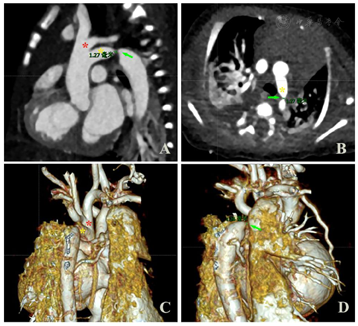

先心病CTA成像:检查所见:1.升主动脉管径约9.6mm。主动脉弓左弓左降。上弓发出头臂干、左颈总、锁骨下动脉;下弓弓降部局部管腔狭窄,管径约0.9mm,长1.5mm,其前后段管径分别约5.4mm、8.5mm,稍远较正常段宽7.9mm,降主动脉(穿膈段)宽6.7mm(图3)。2.房间隔中央部连续性中断,缺损区域大小8.6mm×9.4mm。3.右心房、室增大,右室心肌增厚。4.未见明确降主动脉发出较大侧枝血管影。提示:1.永存第五动脉弓(Weinberg B型),其中下支弓降部缩窄,狭窄后稍显扩张。2.房间隔缺损。3.右心增大;右室肥厚,肺动脉干增宽,超过同层面升主动脉,考虑肺动脉高压。